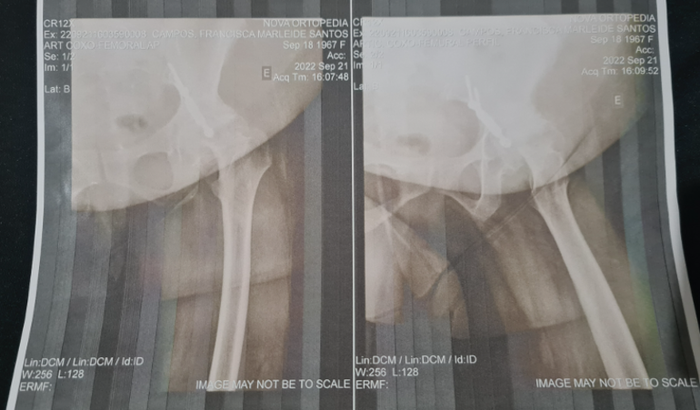

Sofri um acidente de carro em 1992. Com o impacto acabei quebrando o acetábulo e fui operada pela primeira vez e colocaram platina e 7 parafusos. De 20 anos pra cá comecei a sentir muitas dores, fui diagnosticada com artrose. Com decorrer tempo fui piorando cada vez mais.

Meus ossos estão desgastados e agora preciso realizar uma cirurgia para colocar uma prótese na perna esquerda. O valor da cirurgia é 50.000.